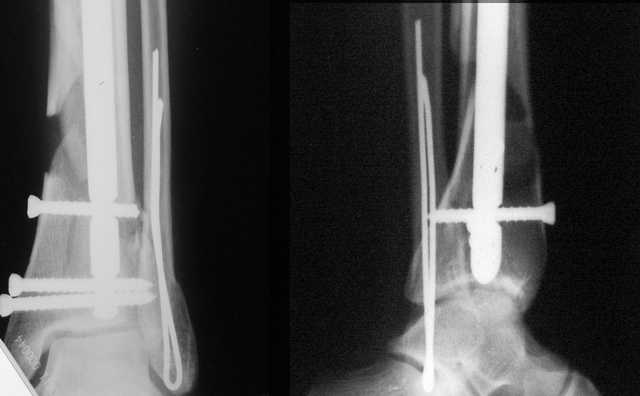

АЧ>Какие тут аргументы в пользу выбора пластины, а не интрамедуллярного гвоздя?

Классически показанием для locked nail яв-ся зоны BC CD, до появления LCP показания к locked nail несколько расширялись в зоны AB и DE

Аргументы: перелом достаточно низкий, трудно будет ввести 3-и блок. винта, а учитывая характер перелома на 2-х дистальных винтах я бы не рекомендовал немедленную полную нагрузку.

С Уважением А.Миронов

Кликните для загрузки файла DSC00841.JPG

42KB (43152 bytes)